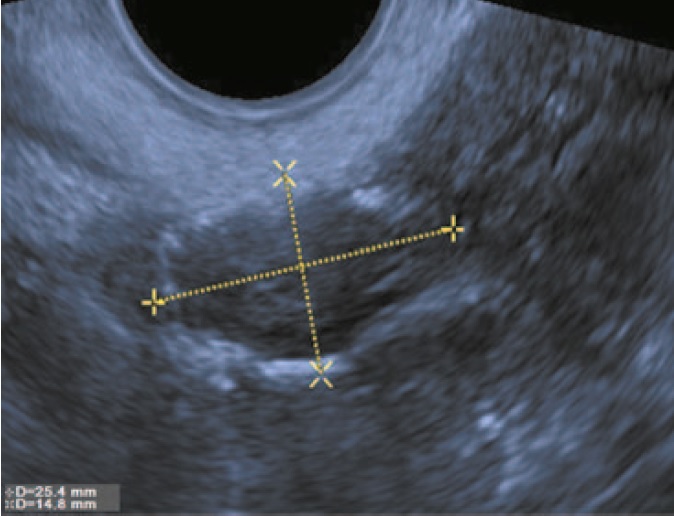

Лапароскопическим доступом больной выполнена биопсия левого яичника. При гистологическом исследовании обнаружена серозная пограничная опухоль. На следующем этапе лечения больной выполнена операция в объеме удаления левых придатков матки, резекции большого сальника. Пациентка находилась под наблюдением. Через 5 лет при УЗИ выявлена опухоль правого яичника. В ходе исследования обнаружено: правый яичник размерами 6,3×4,2 см, в его структуре определяется многокамерное жидкостное образование размерами 4,3×3,3 см, в одной из камер определяются пристеночные солидные папиллярные разрастания толщиной 0,4 см (рис. 3).

Рис. 3. Трансвагинальное УЗИ с использованием эластографии. На изображении неувеличенный яичник. В его структуре определяется тонкостенное кистозное образование с прозрачным анэхогенным содержимым. Пристеночно визуализируются сосочковые структуры толщиной 0,4 см.

Fig. 3. The application of transvaginal sonographic elastography. The ultrasound image showing the normal sized ovary. The structure of the ovary contains thin-walled cystic lesion with clear anechoic contents. A 0.4 cm thick papillary structures lesion along the cyst wall is visualized.